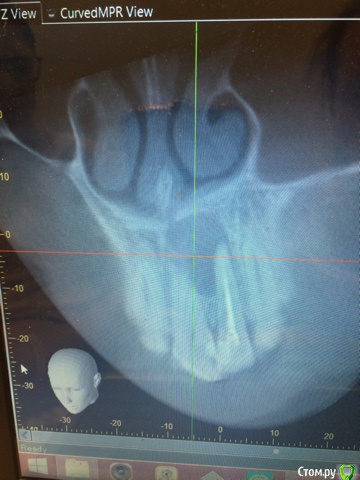

Анна калякина Опубликовано 4 июня, 2017 Поделиться Опубликовано 4 июня, 2017 Здравствуйте! Очень нужна помощь стоматологов!!! Пожалуйста помогите советом!!!В феврале 2017 года на рентгене обнаружена киста корней зубов 21,22После КТ хирург посоветовал удаление двух зубов, терапевт предложил попробовать лечении через канал, за это время меняли лекарство 4 раза ( антисептик и кальций)Каждый раз после введения лекарства десна припухает, в течении месяца отек спадает, но снова меняем лекарство и десна над зубами увеличивается...Лекарство вводим через 22, 21 зуб живой.Пожалуйста посоветуйте что делать дальше. Спустя 3 месяца по рентгену улучшений нет(Спасибо! 1 Ссылка на комментарий